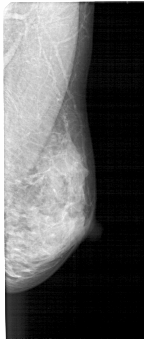

A_1446_1.RIGHT_MLO

RIGHT_MLO LINES 5071 PIXELS_PER_LINE 2146 BITS_PER_PIXEL 12 RESOLUTION 43.5 NON_OVERLAY